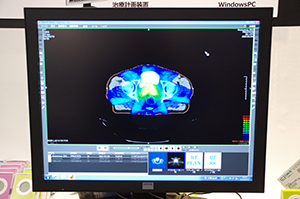

Climb RT Viewerは,

CT画像とRTデータを重ね合わせて表示

Climb RT Viewerは,「院内の誰でも! どこでも!簡単に! 閲覧でき,安価導入!」をうたう,低コストで使い勝手の良さを特長とするビューワ。DICOM Storage,DICOM Q/RなどDICOM規格に対応し,専用サーバを導入することなくPCにソフトウエアをインストールするだけで,CT画像をPACSやモダリティから読み込んで表示させることができる。これにより医療機関は安価での導入が可能となる。さらに,RT Dose,RT Structure Set,DVHといったRT情報を表示させ,CT画像とRTデータを重ね合わせて観察することが可能である。